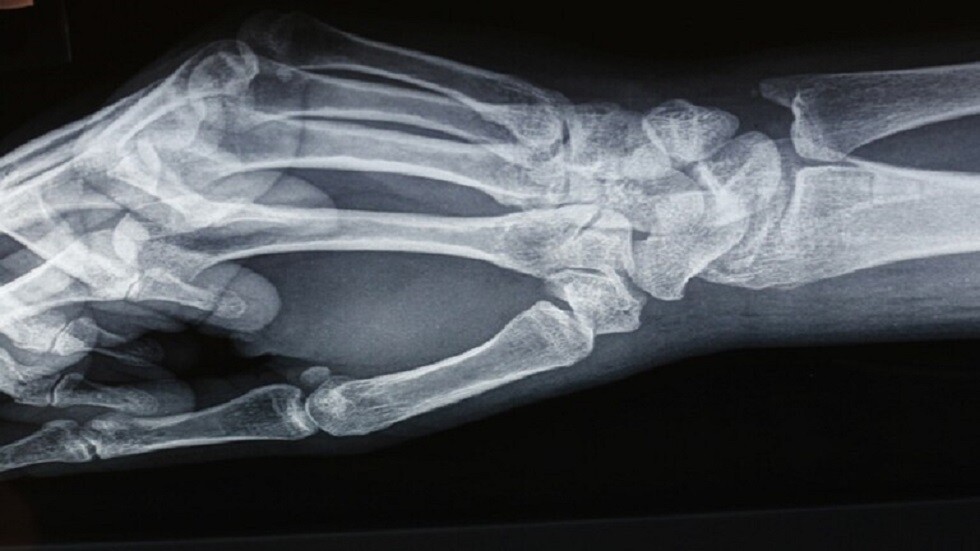

روسيا..ابتكار مادة جديدة لترميم نسيج العظام

ابتكر علماء جامعة كورولوف في سمارا، مادة بيولوجية جديدة لعلاج هشاشة العظام، تسمح ليس فقط باستعادة مكونات النسيج العظمي المعدنية المفقودة، بل والعضوية أيضا.

وتفيد مجلة Journal of Optical Technology، بأن هشاشة العظام، مرض مزمن يصاحبه انخفاض كثافة المعادن تدريجيا في النسيج العظمي، ما يؤدي إلى هشاشة العظام وانكسارها. ووفقا للباحثين يحتل هذا المرض حاليا المرتبة الرابعة بعد أمراض القلب والأوعية الدموية والسرطان ومرض السكري.

ابتكار "ضمادة" معجزة ترمم العظام المكسورة!

وقد تمكن علماء جامعة كورولوف وجامعة سمارا الطبية ومختبر "هندسة الأنسجة" الدولي من ابتكار مادة فريدة جديدة لتصحيح علاج هشاشة العظام- هيدروكسيباتيت (HAP) ، باستخدام تقنية فريدة من نوعها حاصلة على براءة اختراع "ليوبلاست".

وتقول يلينا تيمتشينكو، الاستاذ المساعد في جامعة سمارا، "تحتوي الهيدروكسيباتيت المستخدمة حاليًا على مكونات معدنية فقط، وأما المادة الجديدة فتركيبها يحتوي على مكونات معدنية وعضوية، ما يسمح باستعادة مواد النسيج العظمي المعدنية المفقودة لتصحيح علاج هشاشة العظام والمواد العضوية التي تعتبر إطارا لجميع الأنسجة العضوية"

وتضيف، أظهرت التحاليل التي أجريت أن هذه المادة الجديدة لا مثيل لها في العالم حاليا.

ويشير الباحثون، إلى أنهم أجروا تجارب لدراسة تركيب النسيج العظمي عند الإصابة بهشاشة العظام لمعرفة التغيرات الحاصلة في بنية النسيج في أنواع مختلفة من هشاشة العظام بدءا من المرحلة الأولية وانتهاء بالمرحلة الثانوية.

وتقول تيمتشينكو، "هشاشة العظام الأولية، هي عندما لا تعرف أسباب تطور المرض. أما الثانوية فتظهر عند إصابة الجسم بأمراض معينة. وقد أخذ الباحثون هذه الأمور بالاعتبار ووحددوا معايير فردية لعلاج مرض هشاشة العظام، باستخدام HAP".

المصدر: نوفوستي